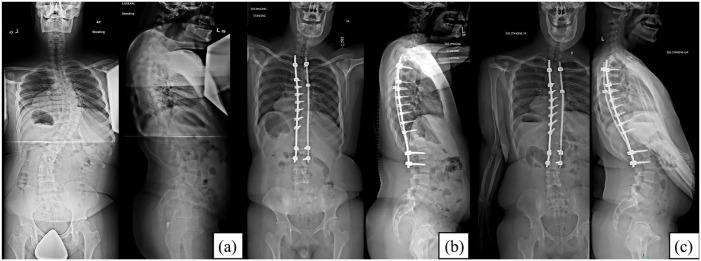

Methods: A retrospective review of 13 patients with Down syndrome who underwent surgical intervention for spinal deformity between 2000 and 2018 were identified. Postoperative complications were classified using the modified Clavien-Dindo-Sink system. Perioperative and final follow-up radiographic data were analyzed.

Results: The mean age at surgery was 14.2 years (11-19) with a mean follow-up of 3.6 years (0.4-6.2) at the time of data collection. Seven (54%) patients had postoperative complications, all related to wound healing. Three patients (23%) had major complications (Clavien-Dindo-Sink grade ≥3). These included one deep surgical site infection, one hematoma, and one seroma, all requiring surgical drainage. Four additional patients (31%) had minor complications (Clavien-Dindo-Sink grade ≤2).